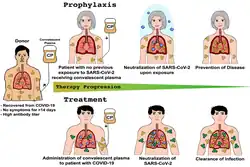

The first COVID‑19 vaccine was granted regulatory approval on 2 December 2020 by the UK medicines regulator MHRA.[203] It was evaluated for emergency use authorisation (EUA) status by the US FDA, and in several other countries.[204] Initially, the US National Institutes of Health guidelines do not recommend any medication for prevention of COVID‑19, before or after exposure to the SARS-CoV-2 virus, outside the setting of a clinical trial.[205][76] Without a vaccine, other prophylactic measures, or effective treatments, a key part of managing COVID‑19 is trying to decrease and delay the epidemic peak, known as "flattening the curve".[206] This is done by slowing the infection rate to decrease the risk of health services being overwhelmed, allowing for better treatment of active cases, and delaying additional cases until effective treatments or a vaccine become available.[206][207]

Vaccine

Knowledge about the structure and function of previous coronaviruses causing diseases like severe acute respiratory syndrome (SARS) and Middle East respiratory syndrome (MERS) accelerated the development of various vaccine platforms in early 2020.[209] In 2020, the first COVID‑19 vaccines were developed and made available to the public through emergency authorizations[210] and conditional approvals.[211][212] However, immunity from the vaccines wanes over time, requiring people to get booster doses of the vaccine to maintain protection against COVID‑19.[210]

The COVID‑19 vaccines are widely credited for their role in reducing the spread of COVID‑19 and reducing the severity and death caused by COVID‑19.[210][213] Many countries implemented phased distribution plans that prioritized those at highest risk of complications, such as the elderly, and those at high risk of exposure and transmission, such as healthcare workers.[214][215]

Common side effects of COVID‑19 vaccines include soreness, redness, rash, inflammation at the injection site, fatigue, headache, myalgia (muscle pain), and arthralgia (joint pain), which resolve without medical treatment within a few days.[216][217] COVID‑19 vaccination is safe for people who are pregnant or are breastfeeding.[218]